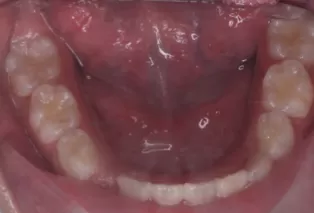

Photos intra-orales